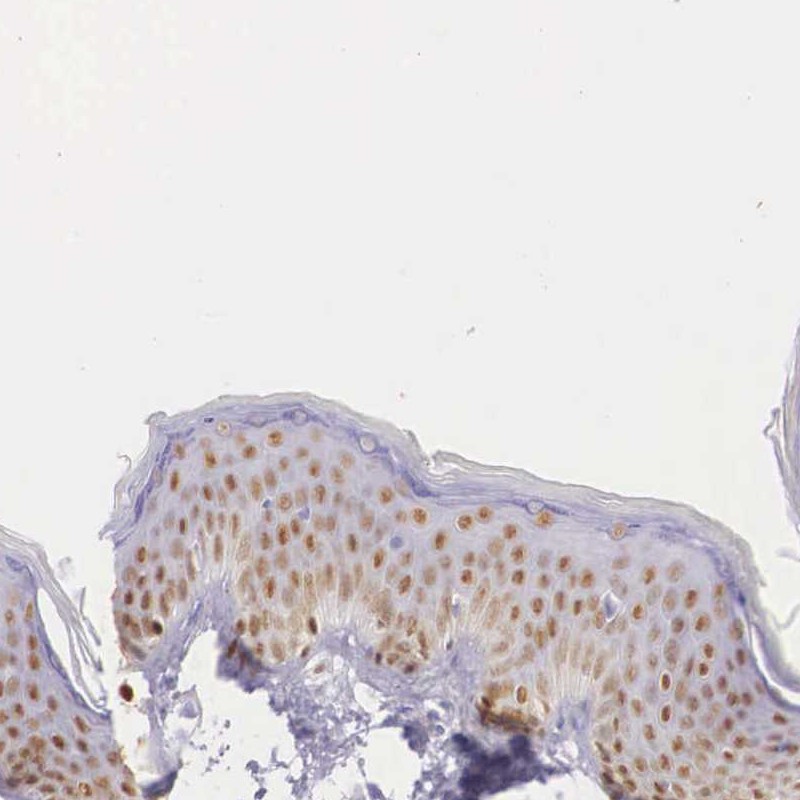

Supportive validation

- Submitted by

- per

- Main image

- Experimental details

- Immunohistochemical staining of human skin shows moderate nuclear positivity in epidermal cells.

- Validation comment

- Staining pattern consistent with experimental and/or bioinformatic data.